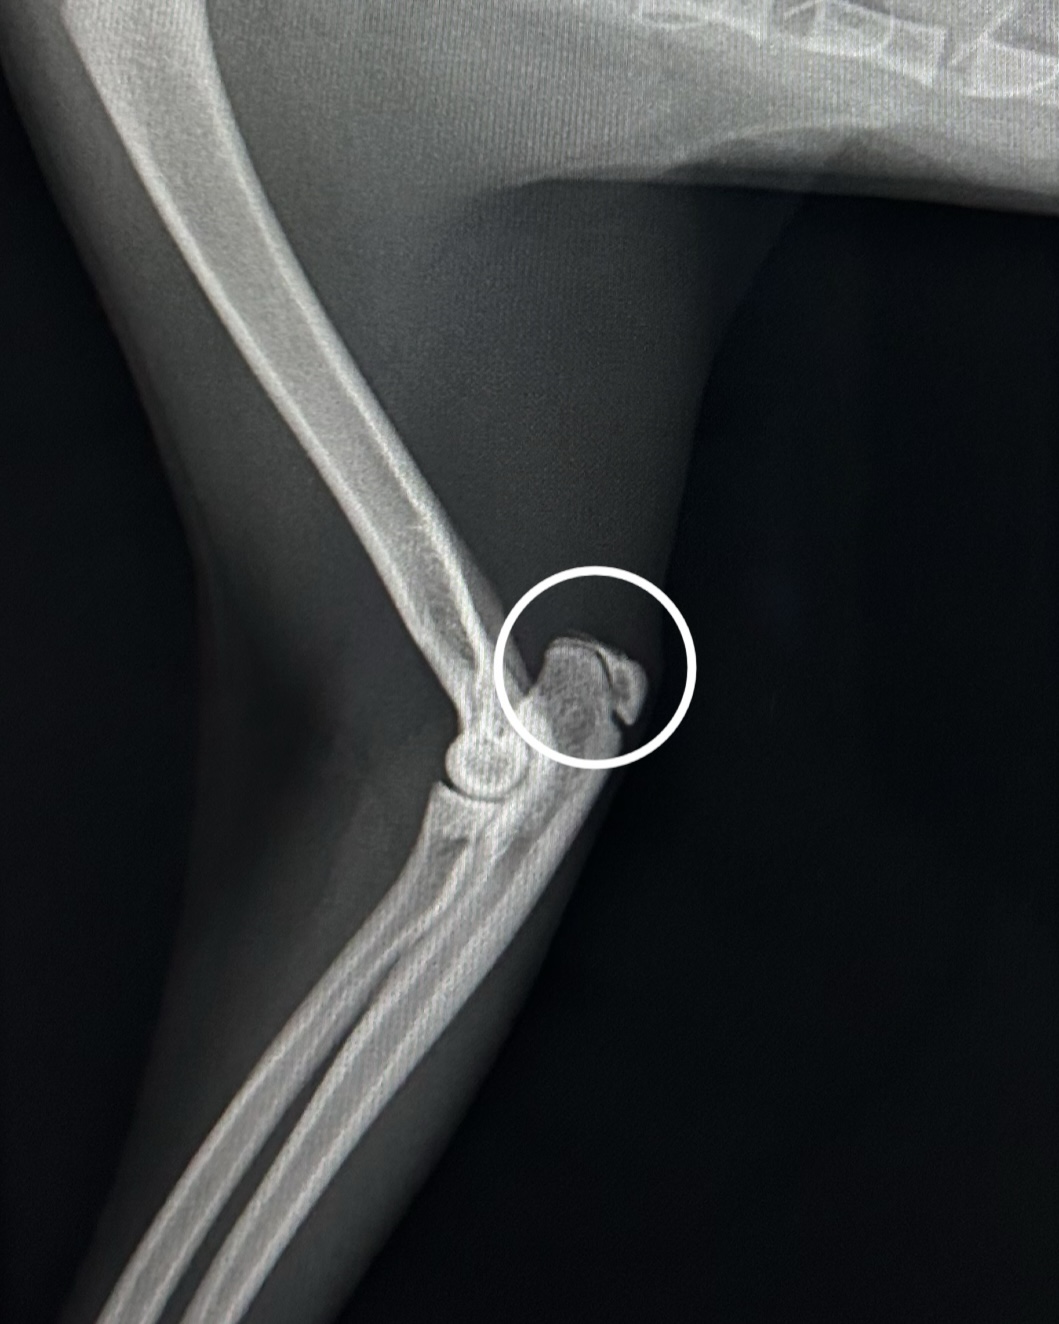

変形した関節(変形性関節炎)

正常な関節(〇は成長中のため亀裂がありますが正常な状態です)